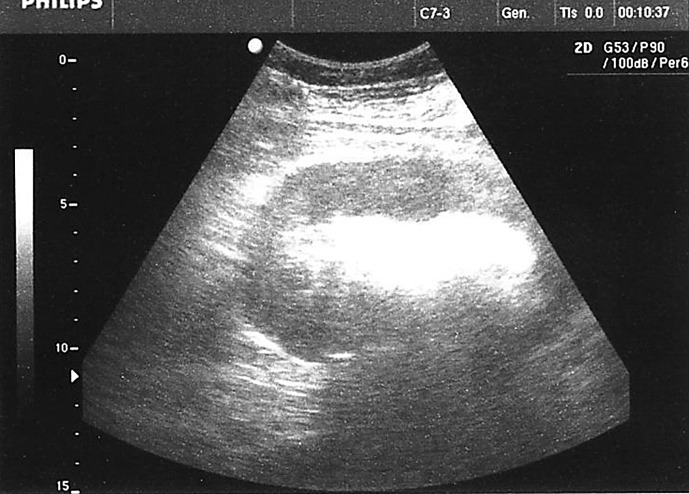

导言:气肿性肾盂肾炎是一种罕见但可能危及生命的尿路感染,其特点是在肾实质、集合系统和肾周组织中形成气体。这种疾病通常发生在有特定易感因素的患者身上,如糖尿病、先天性或后天性梗阻性尿路病或服用免疫抑制剂的患者。在极少数情况下,有其他易感因素(如使用 SGLT2 抑制剂)的患者也会发病,但这种情况并不常见。与使用 SGLT2 抑制剂相关的尿路感染发生率仍有待商榷,但医学文献中已描述了与 SGLT2 抑制剂相关的气肿性肾盂肾炎病例:病例介绍:我们介绍了一例罕见的气肿性肾盂肾炎患者,该患者服用 SGLT2 抑制剂,但没有该病的典型危险因素:尽管使用 SGLT2 抑制剂后发生尿路感染的频率相对较低,但其广泛应用于治疗多种具有重大社会意义的疾病,强调了专科医生有必要了解与使用该药物相关的所有潜在风险,包括发生严重尿路感染的风险。

Introduction: Emphysematous pyelonephritis is a rare but potentially life-threatening urinary tract infection characterized by the formation of gas in the renal parenchyma, collecting system, and perinephric tissue. The condition typically develops in patients with specific predisposing factors such as diabetes mellitus, congenital or acquired obstructive uropathies, or individuals taking immunosuppressive agents. Rarely can the disease occur in patients with other predisposing factors, such as the use of SGLT2 inhibitors, but this is quite uncommon. The incidence of urinary tract infections associated with their use is still debatable, but cases of emphysematous pyelonephritis associated with SGLT2 inhibitors have been described in medical literature.

Case presentation: We present a rare case of a patient with emphysematous pyelonephritis without classical risk factors for the disease, who was taking an SGLT2 inhibitor.